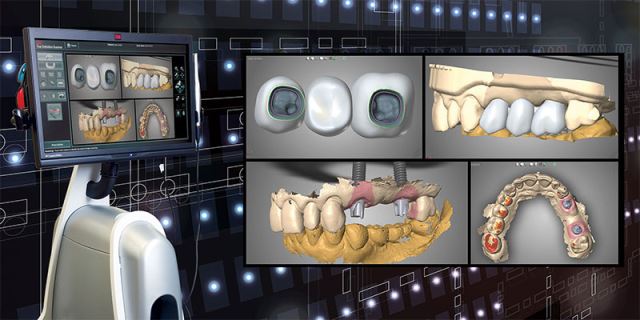

درمان ایمپلنت یک روزه به روش کاملا دیجیتال

برای کاشت ایمپلنت فوری یا ایمپلنت یک روزه، نیازی نیست ابتدا مراحل چند ماهه جوش خوردن ایمپلنت به استخوان را پشت سر بگذارید و پس از آن روکش بر روی دندان تان نصب شود، بلکه در همان روزی که ایمپلنت در دهانتان قرار می گیرد روکش دندان هم بر روی آن نصب می شود. در درمان ایمپلنت به صورت دیجیتال به منظور بررسی استخوان فک و همچنین موقعیت قرار گرفتن رشته های عصبی، از مدل سازی کامپیوتر سه بعدی استفاده می شود. با این شرایط متخصص دندانپزشک با کمترین شکافی به کاشت ایمپلنت دندان می پردازد. به دلیل شکاف کمتر در این روش، درد کمتری برای بیمار وجود خواهد داشت. همچنین به دلیل قرار گرفتن اطلاعاتی بسیار دقیق در دست متخصص دندانپزشک، کمترین میزان آسیب و خطا در این نوع روش درمانی دیجیتال وجود دارد. در کاشت ایمپلنت دیجیتال برای جلوگیری از آسیب عصب و دندان های کناری، یک هدایت کننده (گاید جراحی) بر روی دندان ها نصب می شود. که همین راهنما به برش های دقیق و کوچک تر متخصص دندانپزشک کمک می کند.

در این مرحله به کمک اسکنر دهانی تصویری دیجیتالی تهیه شده که تمامی آناتومی دندان و بافت لثه را ثبت می کند.

برای ضبط دقیق تر آناتومی استخوان و دندان ها، در مرحله ی دوم یک سی تی اسکن پرتو مخروطی انجام می گیرد. در این سی تی اسکن، ساختاری سه بعدی از استخوان، سینوس ها و اعصاب به دست می آید. در ادامه تصاویر مرحله یک و دو با یکدیگر ترکیب شده و از دندان ها و استخوان دهان بیمار، مدلی سه بعدی ایجاد می شود.

در این مرحله پس از بررسی های لازمه قطر و طول ایمپلنت انتخاب می شود. پس از اینکه متخصص دندانپزشک طرح مورد نظر را تصویب کرد، مرحله بعدی انجام می گیرد.

در این مرحله به کمک CAD-CAM یک گاید به صورت قالب پلاستیکی ساخته می شود. این مرحله برای قرار دادن ایمپلنت نهایی بسیار کمک دهنده می باشد. گاید تهیه شده در دهان بیمار قرار داده می شود تا بدون برش ایمپلنت درون جایگاه مورد نظر قرار بگیرد.

در مرحله آخر و در روز جراحی و بلافاصله بعد از قرار دادن ایمپلنت، روکش ایمپلنت که دارای ظاهری بسیار طبیعی و زیبا می باشد، برای بیمار نصب خواهد شد. در واقع در روش ایمپلنت دیجیتال، بیمار حتی یک روز هم بدون دندان نمی ماند.